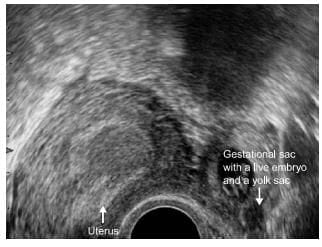

A longitudinal section through the uterus showing a normal early intrauterine pregnancy at 5 weeks' gestation. The sac is surrounded by a well-defined layer of trophoblast tissue and thick decidua.